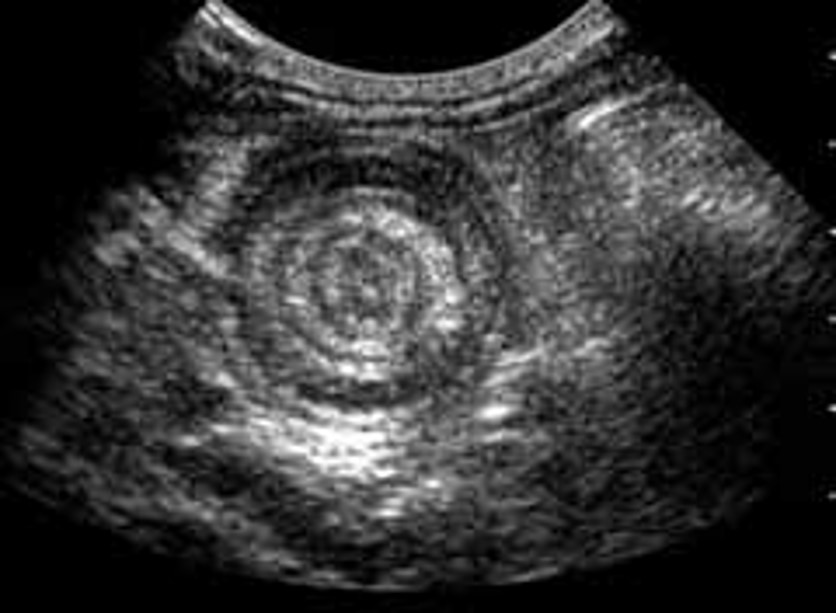

Figure 10. Intussusception – This image shows a transverse plane image of an intussusception. Here, a multi-layered ‘target’ or ‘bullseye’ pattern can be seen, caused by one section of small intestine invaginating within itself.